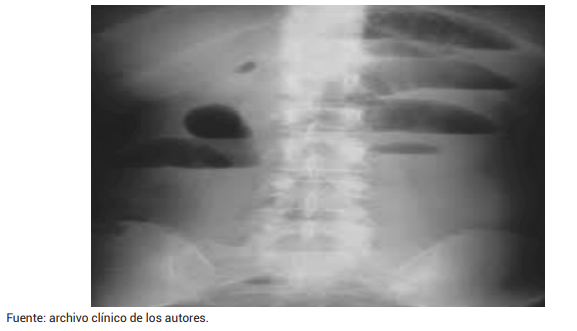

Los paraclínicos realizados en la institución mostraron una marcada leucocitosis con neutrofilia y una elevación de la proteína C reactiva. Además, se realizó una serie de abdomen agudo que reveló una gran dilatación de las asas delgadas, múltiples niveles hidroaéreos, edema parietal, ausencia de gas distal y la falta de neumoperitoneo objetivo (Figura 3).

Figura 3. Radiografía de abdomen de pie con dilatación de asas delgadas, edema parietal y niveles hidroaéreos